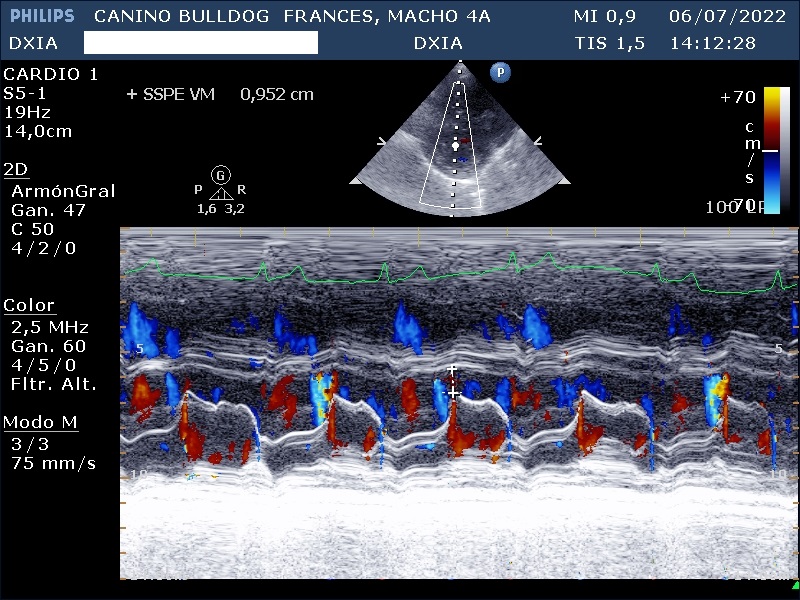

Dilatación marcada de cámaras derechas e izquierdas. SSPE VM: 0,952 cm

AF disminuida en 10,7%

Aplanamiento del septo interventricular.